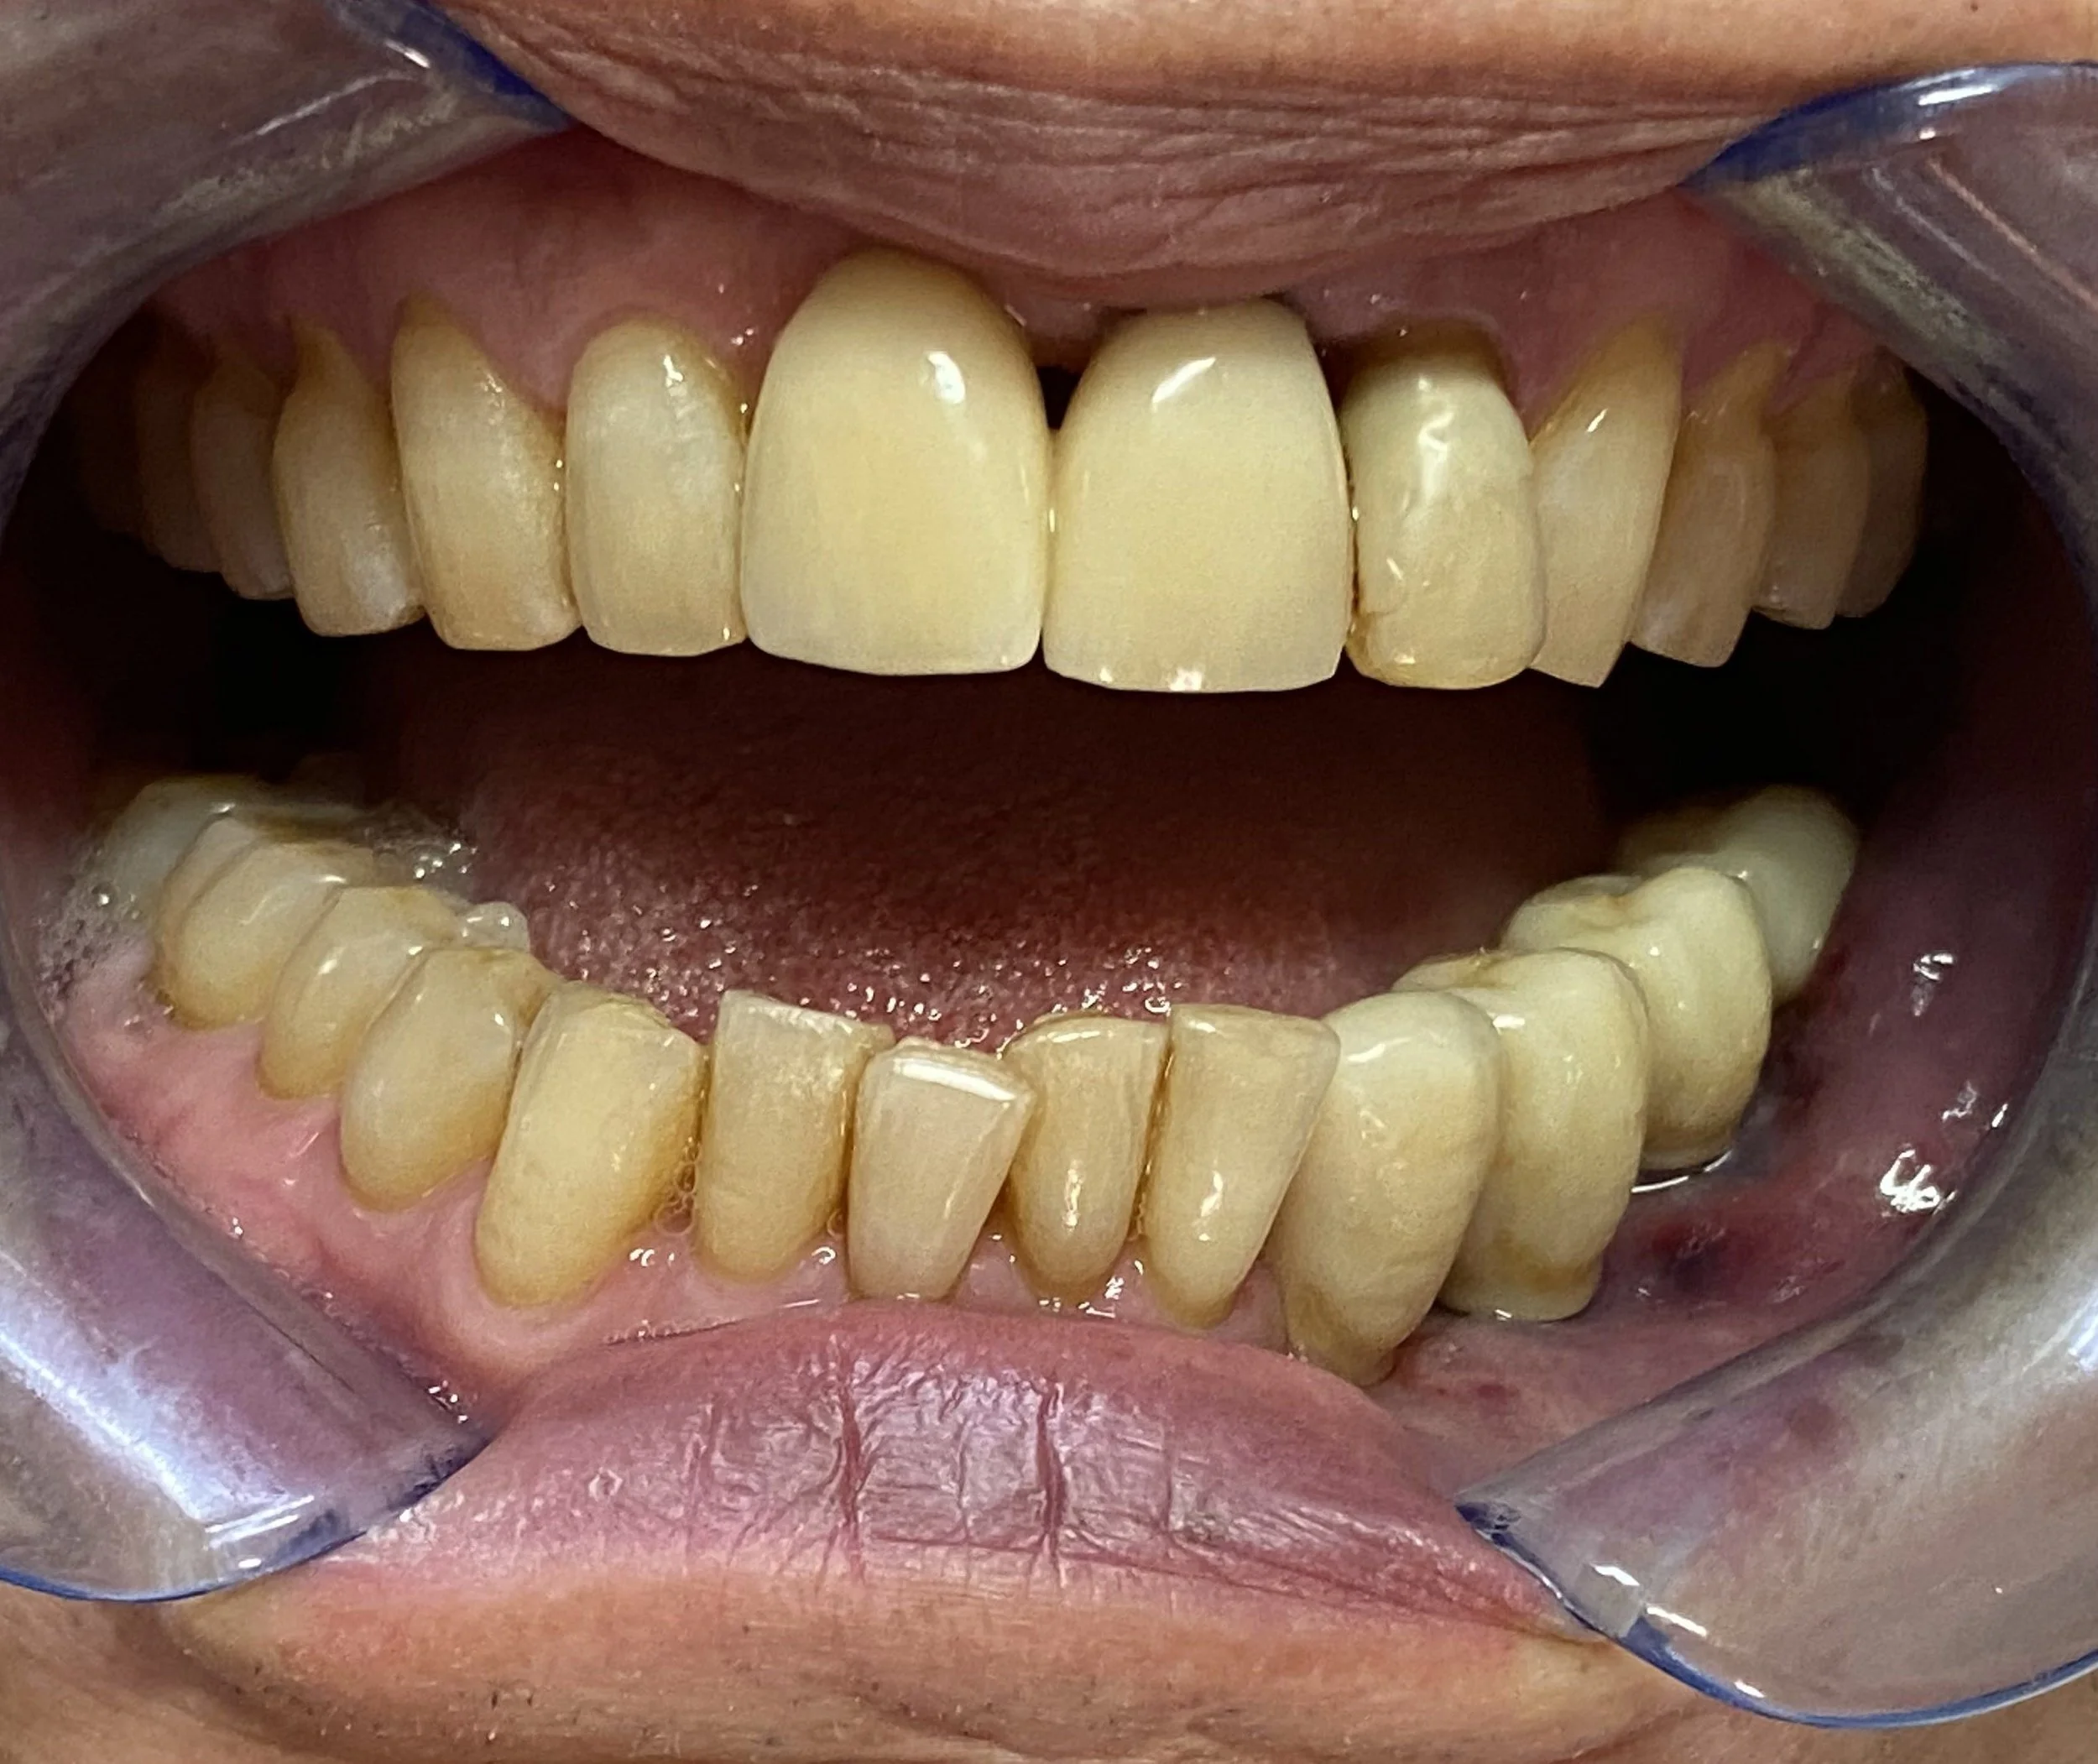

This 65 year old patient had numerous dental problems including decay, periodontal gum disease involving moderate to concerning future bone loss, missing teeth, heavily filled teeth and an extremely difficult very deep overbite.

Part of the deep overbite and a heavily discoloured top left number 2 lateral incisor previously extracted, root sectioned and amalgam filled prior to reattaching as a bonded bridge tooth to the adjacent top left number 3 canine tooth.

The remaining lower 6 front teeth that were deemed to have insufficient bone for longevity and unsuitable for a bite reconstruction, these teeth were extracted.